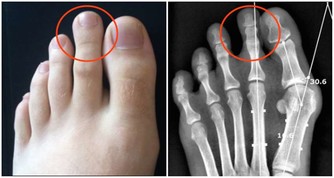

葫蘆素(英語:Cucurbitacin)是從中藥中提取,可治療肝炎及肝癌,存在於深綠色果類或果蒂部位,但誤食過量會有噁心、嘔吐、腹瀉等胃腸道症狀

人們在食用黃瓜時,因黃瓜把兒味苦而往往將其丟棄。其實,這種苦味是由其中含的一種叫葫蘆素的物質引起的,而葫蘆素C是難得的排毒養顏物質。更重要的是,葫蘆素可阻止肝細胞脂肪變性,抑制肝纖維增生,從而可預防原發性肝癌。

1、抗腫瘤

黃瓜中含有的葫蘆素C具有提高人體免疫功能的作用,達到抗腫瘤目的。此外,該物質還可治療慢性肝炎和遷延性肝炎,對原發性肝癌患者有延長生存期作用。